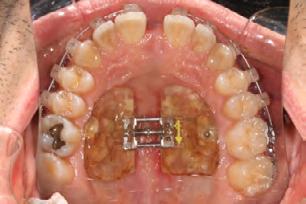

• Surgically assisted rapid palatal expander (SARPE), along with mandibular self-ligating fixed appliances to level, align and upright the mandibular dentition during maxillary expansion.

Palatal mini-implants were placed by a periodontist, followed by placement of the rapid palatal expander (RPE) and bonding of the mandibular arch with self-ligating Damon clear braces. Patient had SARPE surgery performed by the oral surgeon three weeks later (Figure 2), and the expander was turned once a day for three weeks (Figure 3). The maxillary arch was then bonded. Both archwires were incremen-

tally upgraded to an 18 x 25 NiTi wire, and the patient was placed on vertical elastics on the right side. With enough space for the tongue, the lateral open bite began to close.